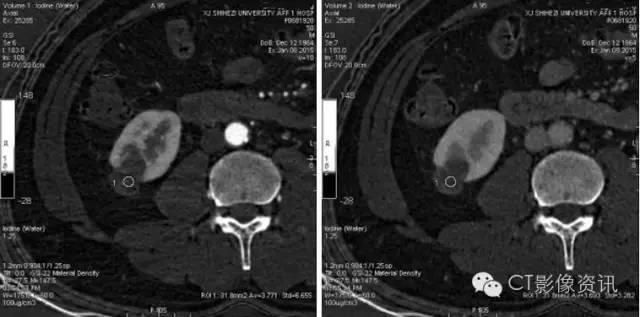

进行能谱分析,碘含量测量,三期病变内部碘含量相似,且接近0的水平,提示病变没有强化。

三期冠状位测量结果显示同样结果。肝实质、肾脏髓质均有明显强化。